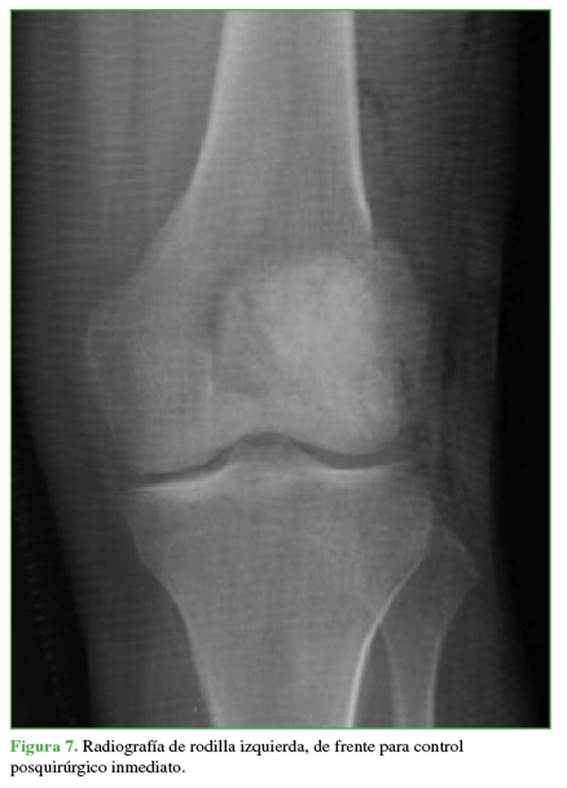

Se realizó una cirugía de curetaje con relleno de hueso de banco y autólogo de cresta, con la que se obtuvieron buenos resultados (Figura 7).

En las radiografías, se observa como una lesión lítica, excéntrica, con origen en la metáfisis. Los bordes geográficos tienen una zona de transición estrecha, sin margen escleroso y con adelgazamiento de la cortical. En la tomografía computarizada, se confirma el adelgazamiento cortical con penetración.